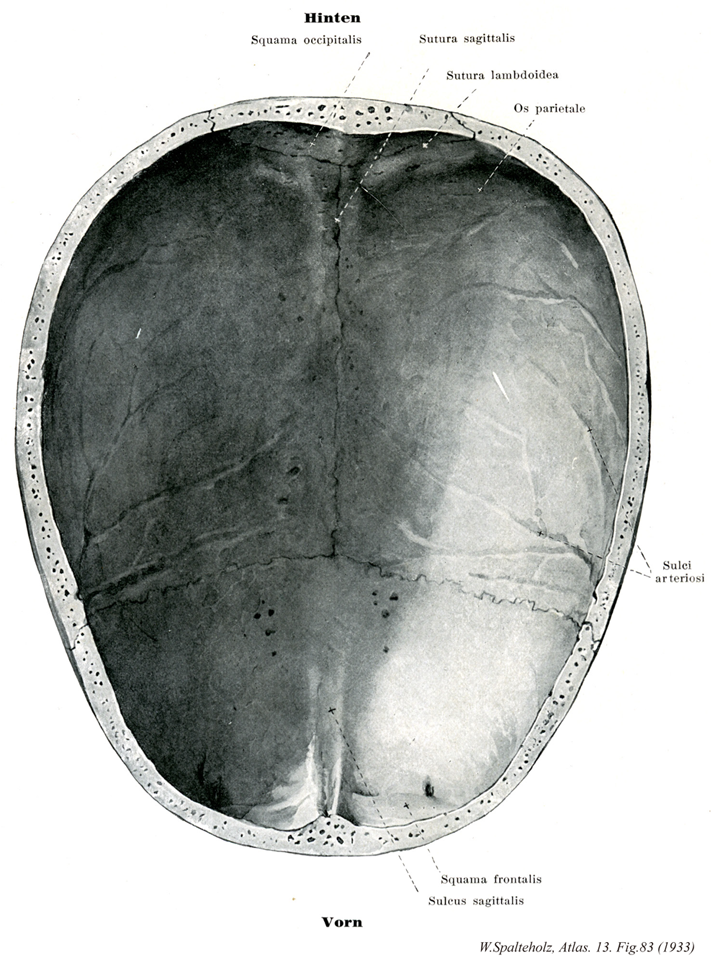

083_00【Calvaria頭蓋冠 Calvaria】 Skull cap, which is curved longitudinally and transversely. It is formed by the squamous parts of the frontal and parietal bones together with the upper portion of the squamous part of the occipital bone. →(頭蓋冠は頭蓋上部を円盤状におおっている部分をいう。全体が結合組織性骨より発生する。頭蓋冠の外面は強い頭蓋骨膜に被われている。頭頂骨、前頭鱗、側頭骨鱗部および後頭鱗からなる。これらの骨は扁平骨で、緻密質からなる外板と内板があり、両者の間には海綿質からなる板間層がある。板間層には静脈間を含んだ板間管があり、外板または内板に開口する。頭蓋冠の平面は平坦で顕著な凸凹は認められず、上面観は卵円形を呈する。前頭骨および頭頂骨の軽度の膨隆を、それぞれ前頭結節および頭頂結節という。側面には上側頭線および下側頭線が認められる。頭蓋冠の前部を前頭、中部を頭頂、後部を後頭という。また両側面で下側頭線より下方の部分を側頭という。底面下面を外頭蓋底という。頭蓋冠の内面に凸凹が多く、脳回による指圧痕、脳溝による脳隆起、中硬膜動・静脈による動・静脈溝がある。また内面には脳硬膜静脈洞によって形成された上矢状洞溝および横洞溝がある。Calvariaはcalvus(はげている)という形容詞に由来する。これ自身が単数形であって、複数形はcalvariaeとなる。)

083_01【Squamous part of occipital bone後頭鱗(後頭骨の) Squama occipitalis】 The part that is posterior to the foramen magnum. →(後頭鱗は大後頭孔の後方にある広い扁平な骨部で、頭蓋冠の後頭の部分と頭蓋底の後部を作る。その縁は不正三角形の広大な鱗状部である。その鋸歯状で大部分はラムダ縫合をもって頭頂骨と接するが、下方では側頭骨とも接する。後頭骨はその大半が軟骨性骨化によって生ずるが、後頭鱗のうち下項線から上方の部分だけは線維性骨窩によって生ずる膜性骨である。しかも後者は数個との骨化中心から出来るので、それら相互の癒合の様子次第で小さい2~4個の、または大きい1個の頭頂間骨(インカ骨)が独立する変異が生ずる。)

083_02【Sagittal suture矢状縫合 Sutura sagittalis】 Suture that joins the right and left parietal bones in the midline. →(矢状縫合は頭蓋冠正中線で左右の頭頂骨を結ぶ。)

083_03【Lambdoid sutureラムダ状縫合;ラムダ縫合;人字縫合 Sutura lambdoidea】 Suture that unites the occipital bone with the two parietal bones. →(後頭骨と左右頭頂骨の間の縫合。ギリシャ文字のラムダ(λ)の形から命名された。矢状縫合がぶつかる点をラムダlambdaといい、胎生期に小泉門があった場所である。(イラスト解剖学))

083_04【Parietal bone頭頂骨 Os parietale】 Bone located between the occipital, frontal, sphenoidal, and temporal bones. →(頭頂骨は正中線で合して頭頂をつくる1対の頭蓋冠の大部分を形成するほぼ四角形の扁平骨で、4縁、4角、2面を有する。4縁のうち後方で後頭鱗接する部分を後頭縁といい人字縫合をなし、下方で側頭鱗に接する部分を鱗縁といい輪状縫合をなす。4角のうち後上角の後頭角は鈍角、後下角の乳突角は鋭角、前上角の前頭角はほぼ直角、前下角の蝶形骨角は鋭角をなす。外面は頭頂面ともよばれ凸面をなし、中央部でとくに膨隆した部分を頭頂結節という。頭頂結節は胎児および若年頭蓋で著明である。また左右両側の頭頂結節間の距離が頭蓋の幅の最も広いところ、すなわち最大脳頭蓋幅径として知られている。頭頂結節の下方に上下2本の弓状の線が認められるが、上の線を上側頭線といい側頭筋膜の着く所である。下の線を下側頭線といい側頭筋の着くところである。矢状縫合の後方部に頭頂孔という小孔があり、ここを頭頂導出静脈が通る。内面は大脳面ともよばれ凹面をなし、指圧痕、脳隆起、動脈溝などが認められ、骨の上縁に沿って幅の広い矢状溝があり、他側の頭頂骨の同名溝と合して完全な上矢状洞溝となる。この近くには多数の小窩があり、クモ膜顆粒をいれる。また乳突角の部分にはS状洞溝の上部の一部が認められる。)

083_05【Arterial grooves動脈溝 Sulci arteriosi】 Bones that are occasionally found interposed in cranial sutures. →(頭蓋内壁にある動脈をいれる溝。)

083_06【Squamous part of frontal bone前頭鱗(前頭骨の) Squama frontalis】 →(前頭骨の前頭鱗は額の骨格をつくり、殆ど垂直に立つ鱗状の部で、その外面はふくれ高まり、内面はくぼむ。これに外面、側頭面および内面の3面がある。)

083_07【Groove for superior sagittal sinus上矢状洞溝;矢状溝(前頭骨の) Sulcus sinus sagittalis superioris】 Prolongation of the frontal crest for the passage of the superior sagittal sinus. →(前頭骨の正中線にある上矢状洞溝は頭頂骨間を走る同名の溝のつづきで、下方に至るにしたがって狭少となる。上矢状静脈洞をいれる。)